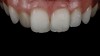

(9.) Preoperative esthetic case documentation using a smartphone and an EALS device.

Figure 9

(10.) Preoperative esthetic case documentation using a smartphone and an EALS device.

Figure 10

(11.) Preoperative esthetic case documentation using a smartphone and an EALS device.

Figure 11

One of the main advantages that smartphone cameras have over DSLR cameras is that nearly everyone is already very familiar with the technology; therefore, the incorporation of these devices into everyday practice does not require learning a new and unfamiliar skill set. The task of producing a series of high-quality clinical photographs for routine examinations (Figure 8), esthetic treatment planning (Figure 9 through Figure 11), or specialty care (Figure 12 and Figure 13) can be delegated with confidence to any staff member during the patient's initial office visit and will generally require less than 5 minutes of time to complete. When a DSLR camera is used, evaluation of the intraoral images either takes place on the small viewfinder built into the camera or necessitates the physical removal of the memory card from the camera to downloaded the images onto a computer for review. An added bonus of smartphone dental photography is that the phone's screen now replaces the much smaller viewfinder of a DSLR camera and provides the clinician with the ability to view and zoom into the patient images on a 5- to 6-inch, high-definition display.